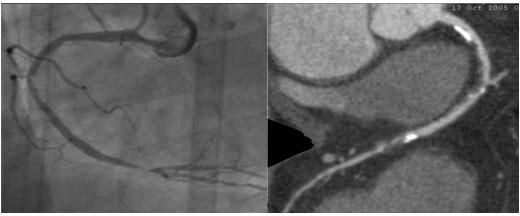

64排螺旋CT冠狀動脈血管成像:

1、簡單:無需經動脈插管,隻需象平時靜脈輸液一樣在肘靜脈内推注相對适量對比劑,然後行快速掃描即可完成整個檢查。

2、安全:64排螺旋CT冠狀動脈造影,對比劑用量較少,無需動脈插入導管,患者無需承擔麻醉及動脈插管等帶來并發症的危險。在冠狀動脈血管疾病的篩查、早期診斷、冠狀動脈成形術和搭橋術前、術後血管評價,冠狀動脈起源異常及心肌橋等方面極具優勢。

3、後處理功能豐富:西門子公司爲SOMATOM Definition AS+ 128層4D螺旋CT配備了功能強大的後處理工作站:MMWP(多産品工作站)和最新型的醫學影像IT工作平台,Syngo.via,智能,便捷。

CT冠脈血管成像:

1.冠脈軟斑塊:

2.混合性斑塊:

3.對于斑塊性質的确定,CT優于DSA: